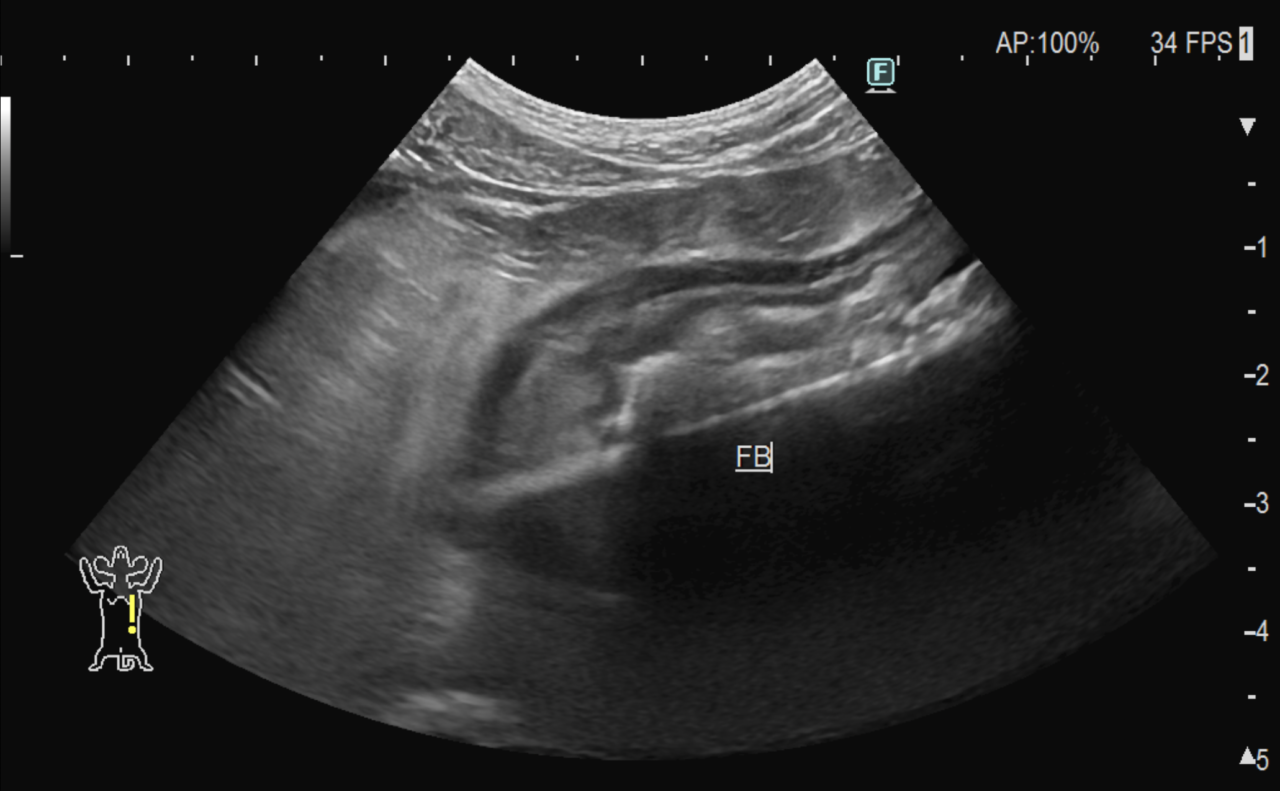

1週間前に団子を串ごと誤飲した可能性があるワンコが急にぐったりしているとのこと。すぐに地元の救急病院を受診すると異物による胃穿孔が疑われました。外科的な摘出と腹膜炎によるクリティカルケアが予想されたため紹介来院しました。開腹後、竹串による胃穿孔が確定されました。腹膜炎も同時に起こっています。穿孔創を封鎖し、腹腔洗浄とドレインの設置を行いました。幸いにも48時間後に食欲が出て退院となりました。愛犬が竹串を誤飲してしまったら、命に関わる事態に発展する可能性もあるため、早めに内視鏡による摘出をお勧めします。このような異物を発見するためにはエックス線よりも超音波検査が非常に有効です。